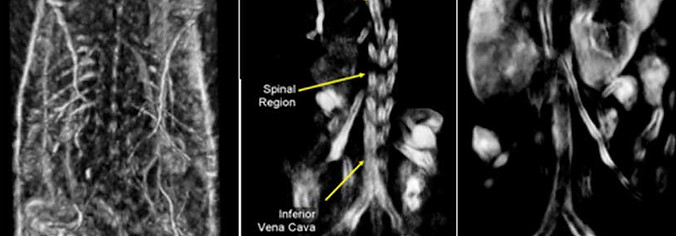

TomoWave Medical Group is dedicated to advancing and applying cutting-edge 3D/4D Photoacoustic Tomography (PAT) technology. This innovative technology enables structural, functional, and molecular imaging through its exceptional resolution, contrast, and sensitivity. It facilitates real-time, image-guided animal experiments and enables non-invasive, synchronous image-guided biopsies and surgeries. As a leader in the research, development, and production of photoacoustic tomography imaging equipment, TomoWave has successfully launched two pioneering product lines: the Preclinical Animal Photoacoustic Imaging System and the Clinical Photoacoustic Diagnostic System. Notably, the Preclinical Animal Photoacoustic Imaging System has achieved significant commercial success, with sales exceeding 3.5 million USD.